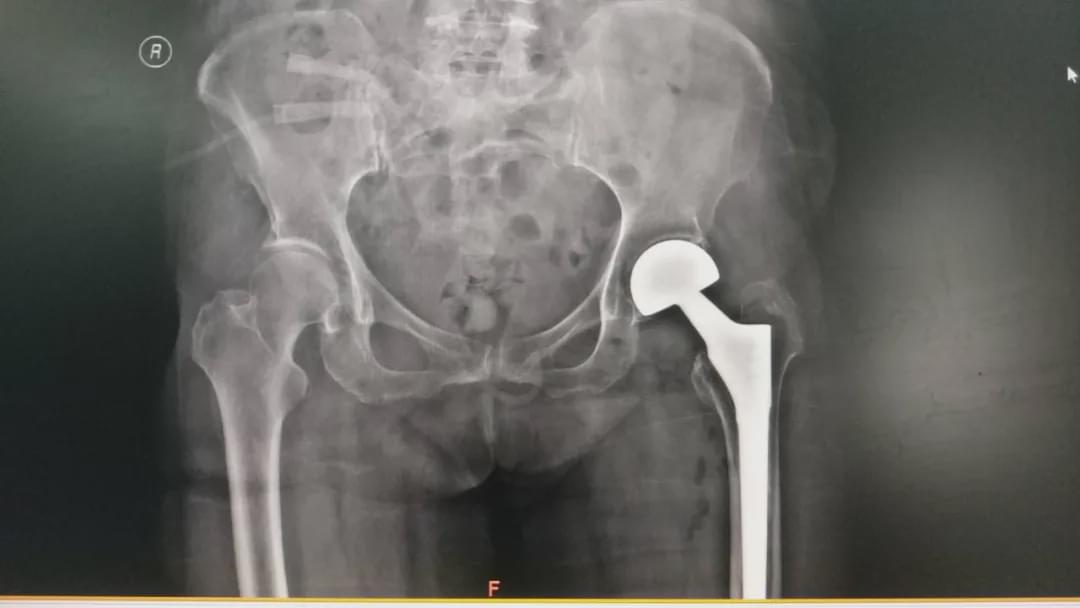

駐馬店市的臧女士,今年80歲,十余年前因股骨頸骨折行左側(cè)人工股骨頭置換術(shù)。近日,不慎摔傷導(dǎo)致左髖部疼痛、不能活動(dòng),當(dāng)時(shí)未給予檢查及治療,自行在家臥床休息,幾天后,癥狀無(wú)緩解。9月2日被家屬送到駐馬店市中心醫(yī)院就診,經(jīng)過(guò)接診醫(yī)生檢查,診斷為“左側(cè)人工股骨頭置換術(shù)后假體松動(dòng)”。隨后到關(guān)節(jié)外科住院治療。

根據(jù)臧女士的病情,關(guān)節(jié)外科高山主任及主治醫(yī)師李張等人共同為患者制定了周密的治療方案,在手術(shù)部及麻醉科配合下,為她施行“左側(cè)人工髖關(guān)節(jié)翻修術(shù)”。經(jīng)過(guò)2小時(shí)的共同努力,手術(shù)順利完成,術(shù)后患者生命體征平穩(wěn),且無(wú)任何不適,在醫(yī)護(hù)人員的正確指導(dǎo)下,患者術(shù)后第1天抬腿、第2天下床活動(dòng),明顯縮短臥床時(shí)間,經(jīng)過(guò)治療于9月12日康復(fù)出院,得到了患者及家屬的感謝。(南媛媛 李沐佳)